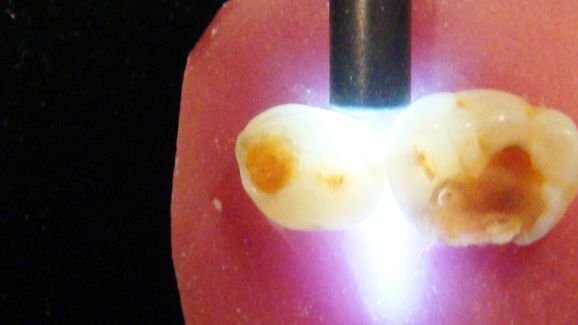

La sensibilité d'une méthode de détection est liée à sa capacité à détecter la maladie lorsqu'elle est présente, et sa spécificité est liée à sa capacité à détecter l'absence de la maladie quand elle n'est pas présente. La détection de la carie occlusale est compliquée cliniquement due à la morphologie de la surface, l'exposition au fluorure dans le passé, la topographie de la fissure anatomique et la présence de plaque et de taches. Les méthodes couramment utilisées sont l'inspection visuelle et tactile, la radiographie, la transillumination et la fluorescence laser. Cette dernière, à savoir le DIAGNOdent (KaVo), est encouragée pour la détection de lésions à la fois occlusales et interproximales. Sa technologie est basée sur la fluorescence de porphyrines excitées par une lumière laser, à une longueur d'onde de 655 nm. La sensibilité et la spécificité de la fluorescence laser pour détecter les lésions intra-dentinaire varie considérablement, avec des faux positifs, problème principal de la technologie. Afin d'obtenir les meilleurs résultats, l'angulation de la pointe doit être consistante et les résultats devraient être évalués avec d'autres méthodes de détection.

Les systèmes les plus récents de fluorescence induite par la lumière quantitative (y compris QLF, Inspektor Research Systems, et SOPROLIFE, Actéon) utilisent des différences dans l'auto-fluorescence entre le son et l'émail et la dentine déminéralisée. L’émail déminéralisé paraît plus sombre que la structure de la dent saine adjacente, et la dentine cariée apparaît en rouge en fonction des filtres utilisés. L'utilisation du QLF (longueur d'onde 405 nm) permet la détection précoce de la déminéralisation de l'émail et il peut être utilisé pour distinguer entre la dentine affectée et infectée. Comme le DIAGNOdent, la technologie QLF est tributaire de techniques standardisées, en particulier du contrôle de la lumière ambiante, et les résultats doivent être considérés en conjonction avec d'autres méthodes. Le SOPROLIFE utilise une longueur d'onde de 450 nm, et présente les paramètres pour le diagnostic de la dentine cariée ainsi qu'un mode de traitement, ce qui aide à déterminer quelle dentine doit être supprimée.

Le procédé de la transillumination par fibre optique est basé sur le principe que la structure de la dent saine a un indice plus élevé de transmission de la lumière qu’une dent cariée. Des unités, telles que la pointe de diagnostic SDI pour l'unité de photopolymérisation SDI ou la pièce à main de transillumination NSK sont simples à utiliser. La source de lumière est placée sur la face vestibulaire ou linguale de la dent. La transillumination est principalement utilisée pour la détection des lésions carieuses proximales, bien que des études aient montré qu'elle peut aussi améliorer la détection visuelle des lésions occlusales. Les lésions carieuses limitées à l'émail apparaissent comme des teintes grises, et celles de la dentine apparaissent comme des teintes de brun-orange ou de bleu.